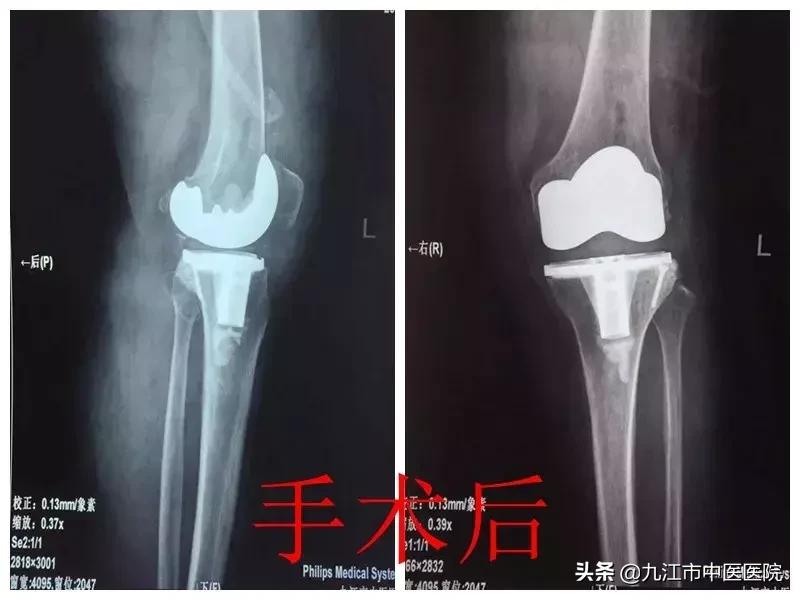

在和家属充分沟通并取得同意后,经过术前反复论证,最终选择采用适当的截骨与松解技术,根据患者关节稳定程度选择了稳定型膝关节假体。手术非常顺利,术后患者膝关节疼痛减轻,膝外翻畸形纠正,72小时后即可在家人搀扶下下地行走,无任何神经受累症状,目前已恢复正常生活自理活动,正在康复中。